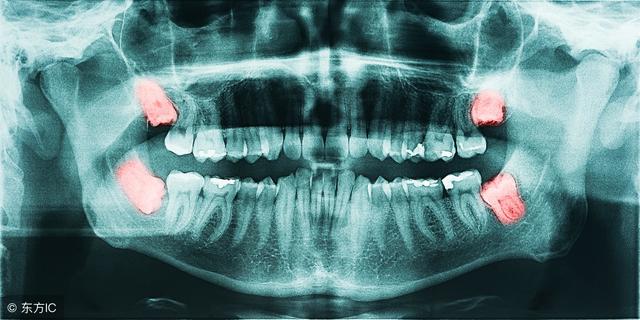

智齿就是口腔中的最后面的臼齿,有人会长,有人终生都不会长。不少人体验过智齿犯了,会疼的要命。

智齿的危害有哪些?

1. 影响正常咬合。阻生智齿的生长位置是不够的,也没有对应对颌牙齿,使之不能建立正常的咬合关系,长时间就会导致张口疼痛、磨牙等症状,对青壮年的身心影响较大。

4. 邻牙拥挤和松动。由于智齿的长歪没有足够的空间生长,就会挤压到相邻的牙齿,使相邻的牙齿松动,产生牙痛出血等症状。